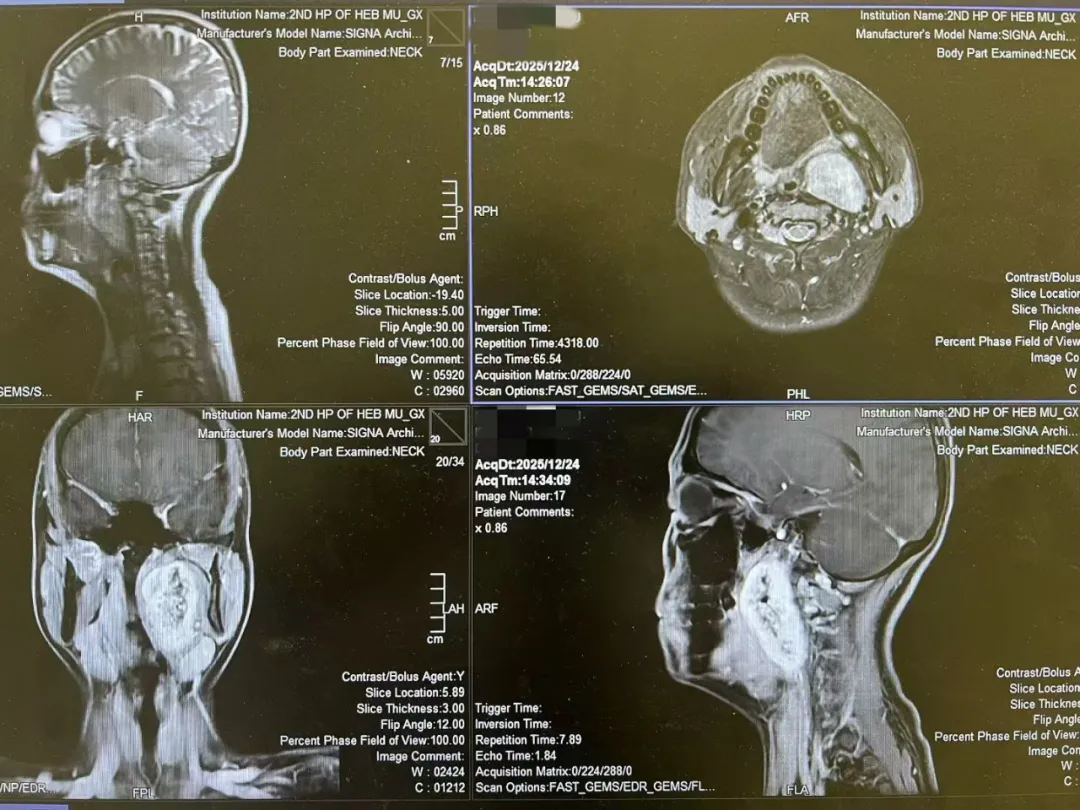

患者是一位年轻的女孩,咽旁间隙,七厘米的巨大肿物。像一颗沉默的炸弹,深藏在颈侧的重重屏障之后——肌肉、血管、神经、下颌骨。

辗转数家医院,得到的方案都指向同一条路:颈外入路。那意味着,需要在颈侧留下一条不可避免的疤痕,甚至可能劈开下颌骨。对于一位风华正茂的姑娘来说,这道疤痕,或许和肿瘤本身一样沉重。她最终找到了我,或者说,选择了我们团队尝试的另一条路:经口入路。

当它离开体腔的那一刻,手术室里没有欢呼,只有一声长长的、共同的呼气。护士测量后轻声说:“张老师,直径真的超过七厘米。” 我看着托盘里的肿瘤,再看向女孩安静的面容——她的下颌完好,颈部肌肤光滑如初。